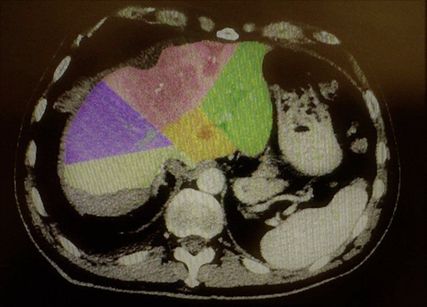

Abb. 2: Große zentrale Metastase eines Rektumkarzinoms (rosa Bereich) sowie sehr kleine linkslaterale Segmente (grüner Bereich)

Welches Verfahren zur Augmentation des FLR genutzt werden sollte, ist aktuell nicht klar festgelegt. Sparrelid E et al. haben die PVE mit dem ALPPS-Verfahren bei kolorektalen Lebermetastasen verglichen und konnten zeigen, dass der Hypertrophieeffekt des ALPPS-Verfahrens (Abb. 2 und Abb. 3) signifikant besser war (66,7% vs. 46,3%; p=0,001).7 Den besten Hypertrophieeffekt hatte jedoch die primäre PVE gepaart mit einer Rescue-ALPPS. Die Rate der erfolgreichen Resektionen war ebenso im ALPPS-Arm höher, jedoch statistisch nicht signifikant (84,5% vs. 73,2%; p=0,08).